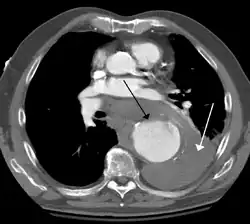

Contrast enhanced CT of a ruptured large (7 cm) thoracic aneurysm, with black arrow indicating the aorta, and white arrow blood in the thorax